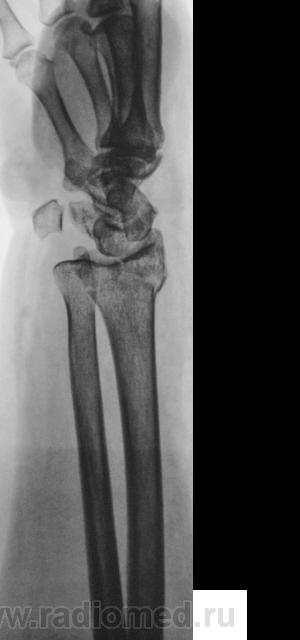

Травма.   Пациент направлен на рентгенографию лучезапястного сустава.

СЛУЧАЙ № 1.